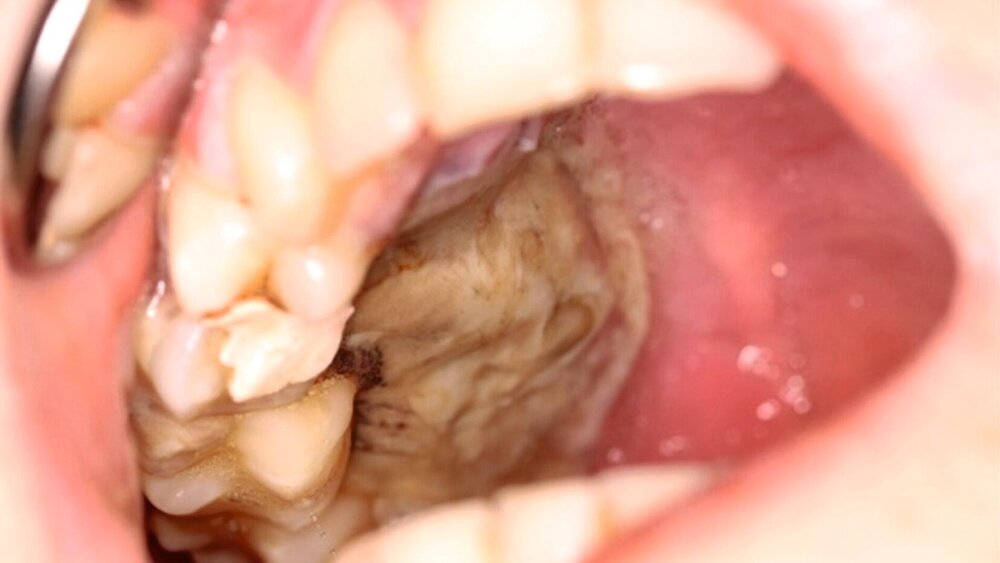

Die klinische Untersuchung zeigte eine ausgeprägte nekroische Schleimhaut palatinal und vestibulär regio 15 bis 17, einen stark gelockerten Zahn 15 sowie einen intensiven Foetor ex ore bei einer auf 2,5 cm eingeschränkten Mundöffnung (Abbildung 1).